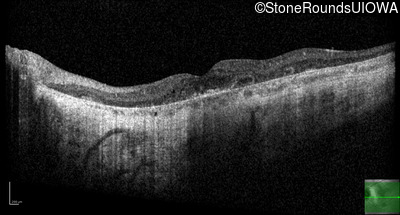

This 46 year old man first had difficulty driving at night in his mid-thirties. Clinically focused genetic testing for Choroideremia was negative.

| XL Choroideremia | CHM | Insertion of 212.3kb of Chr. 3 in intron 2 (IVS2+15,016 ins 212.3kb) | XL |